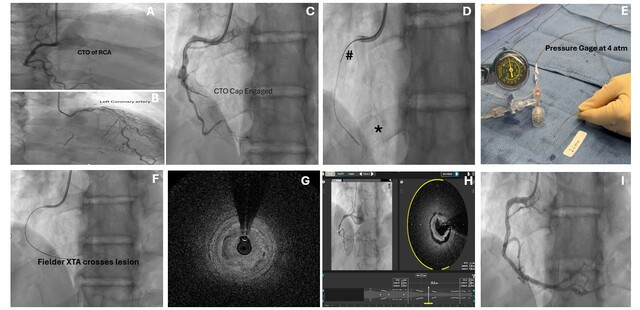

A 69-year-old man was referred for percutaneous coronary intervention (PCI) of a right coronary artery (RCA) in-stent complete total occlusion (CTO) (Figure A), which had collateral supply from the left anterior descending artery (Figure B).

Primary HydroDynamic contrast recanalization (HDR) was performed using a 7F Judkins Right-4 guide catheter (Medtronic). The tip of a Corsair Pro microcatheter (ASAHI INTECC) was advanced into the proximal cap over a 0.14-inch Runthrough wire (Terumo) (Figure C), and was followed by injection of droplets of contrast, utilizing a pressure gauge inflator and limiting the pressure to 4 atm (Figure D and E). Following contrast injection, a 0.14-inch Fielder XTA (ASAHI INTECC) successfully crossed into the distal RCA (Figure F). A DeepOCT+NIRS catheter (SpectraWAVE, Inc.) was then advanced.

Optimal computed tomography revealed that contrast had penetrated inside the plaque of the CTO in a circumferential pattern (Figure G, Video). Predilatation of the lesion with a compliant ballon led to a 360-degree intimal dissection (Figure H, Video); this may be related to the pattern of plaque modulation by HDR leading to injury of structurally weaker areas within the obstruction.

Ultimately, the patient underwent successful PCI of the RCA with a drug-eluting stent (Figure I) and was discharged home.